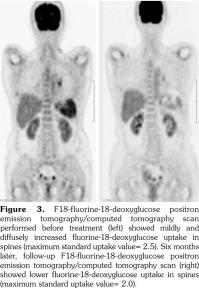

A 53-year-old female patient suffered from pain over most of her body, particularly the joints and the throat. In addition, skin rashes on the trunk without pruritus were noted. She had visited the Rheumatology, Neurology, and Orthopedic Outpatient Department several times. A chest computed tomography (CT) was performed which revealed multiple lymphadenopathies over cervical, mediastinal, and axillary areas. A positron emission tomography (PET)/CT revealed increased fluorine-18-deoxyglucose (FDG) uptake in many lymph nodes including the bilateral neck, axillae, mediastinum, bilateral pulmonary hili, abdominal paraaortic region, iliac regions, and inguinal regions as well as the bone marrow and the spleen (Figure 1). In addition, mild and diffuse increase of FDG uptake in the bone marrow was noted. Lymphoma was suspected first. After discussing with the patient, thoracoscopic mediastinal lymph node biopsy was performed. Fifteen lymph nodes were taken and the results showed histiocytic infiltration in sinusoid area and anthracotic pigment deposition. Reactive lymphoid follicle hyperplasia and focal fibrocalcified nodule formation were also noted. No tumor cell was seen. Gallium-67 (Ga-67) scan was conducted and no gallium-avid tumor was seen throughout the whole body (Figure 2). The laboratory data were negative for antinuclear antibodies, rheumatoid factor- immunoglobulin M, and extractable nuclear antibody, while alanine aminotransferase was high. The final diagnosis was AOSD. In our case, there were no symptoms or signs of either high fever or debilitating joint although the FDG PET showed multiple FDG-avid lesions in the whole body scan. According to the experience of our rheumatologists, methylprednisolone (Metisone) 4 mg/day and non-steroidal anti-inflammatory drugs were prescribed initially and the response to treatment was good. Six months later, the follow- up PET/CT showed complete remission of the FDG-avid lesions seen in the previous PET/CT (Figure 1) and the patient’s symptoms relieved. A written informed consent was obtained from the patient.

In this study, we present the FDG PET/CT and Ga-67 scan findings of a patient who met the Yamaguchi classification criteria for AOSD. The FDG PET/CT scan was not helpful in diagnosing AOSD in this case since lymphoma could not be ruled out. However, the FDG PET/CT scan results were useful for evaluating the distribution and severity of the disease. A negative Ga-67 scan could be beneficial as it would exclude lymphoma. After the diagnosis of AOSD was established, the patient received nonsteroidal anti-inflammatory drugs and glucocorticoids with a good response. Disease activity and therapeutic response were monitored by FDG PET/CT and the findings of a scan performed six months after treatment were negative.(13)

The treatment of AOSD remains largely empirical, relying so far on a few prospective or retrospective studies and not on double- blinded randomized trials with suitable sample sizes.(12) In our case, there were no symptoms or signs of high fever, debilitating joint or life- threatening complications although the FDG PET showed multiple FDG-avid lesions in the whole body scan. According to the experience of our rheumatologists, low dose of corticosteroids was prescribed first and the response to treatment was good. The patient’s symptoms and signs relieved and the follow-up PET/CT showed complete remission of these FDG-avid lesions six months later.